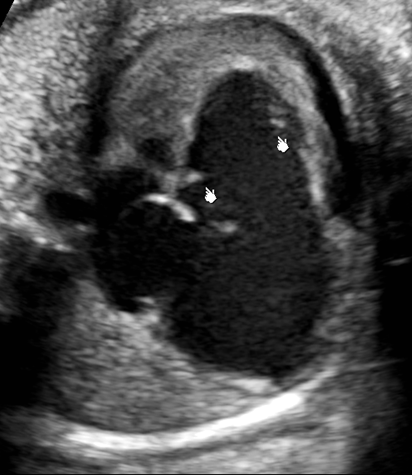

Systole AVSD [different sizes of atrium]

Diastole AVSD